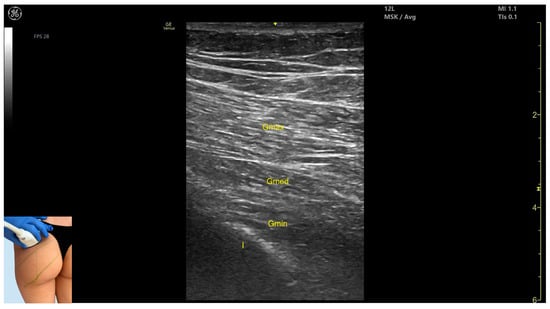

3.1.2. Ultrasound Identification

3.1.3. Key Ultrasound Landmarks

- Muscle morphology: It is the strongest and most superficial muscle in the gluteal group.

- Muscle position: It represents the most superficial muscle mass at this level. It lies superficial to both the gluteus medius and gluteus minimus.

- External fascia: It is enclosed by a pronounced fascia, which separates it from the subcutaneous tissue and the gluteus medius, facilitating botulinum toxin injection.

- Dynamic evaluation: During dynamic evaluation, scanning laterally toward the hip joint reveals an increase in muscle thickness of the gluteus medius and gluteus minimus. Muscle contraction is visible during hip extension and external rotation maneuvers.

| Gluteus Maximus | Upper gluteal region; 8 cm lateral to sacrum | Gluteus medius and minimus (deep); sciatic nerve (potentially) | Scan angled at 45° toward the sacrum | Avoid sciatic nerve injury |